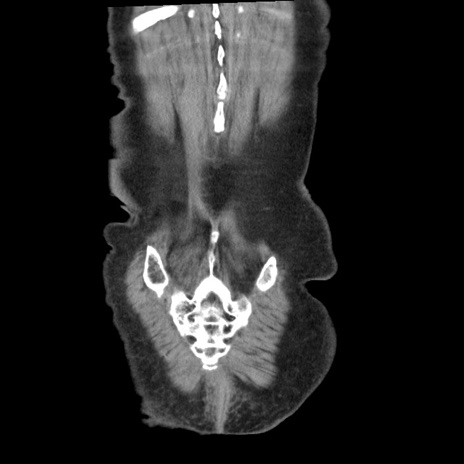

症例1(冠状断像)

矢状断像